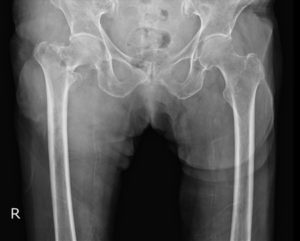

整形外科